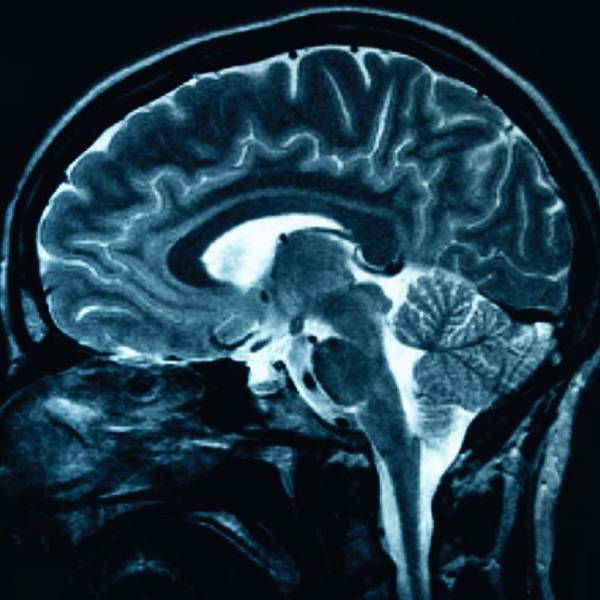

El DIPG (siglas en inglés) suele afectar a niños de entre cuatro y nueve años, los cuales pierden paulatinamente el control muscular a medida que el tumor ataca, con rapidez, el puente o protuberancia, una región del tronco encefálico que conecta el cerebro con la médula espinal.

Este tipo de tumor es difícil de alcanzar y eliminar quirúrgicamente y, a pesar de los tratamientos con radiación, normalmente los niños no suelen sobrevivir más de nueve meses y menos de un uno por ciento lo hace más de cinco años.